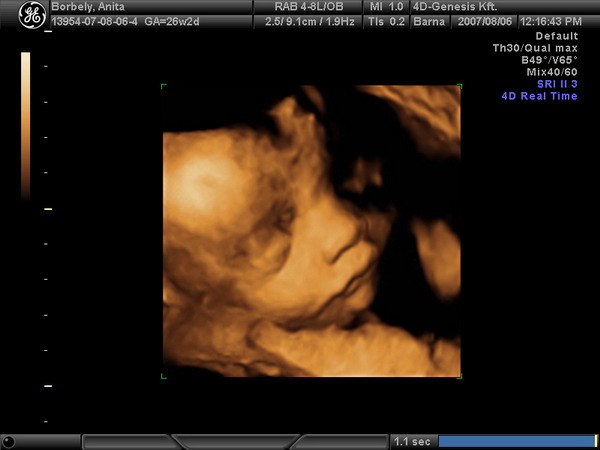

Mi is menni fogunk 4D-re de szerintem valamikor a 20. hét után. Mutatok nektek egy nagyon aranyos 4D képet Aporról. :)

Anika, naggyon szép a 4D kép... A spermiumok valóban ne, élnek 48-72 órán túl, de ha már talélkoztak a sejtek, utána még keringhet 1 -2 napig, a beágyazódás volt lehet egy kicsit később, de nem 1 héttel később, az tuti.

Anika, gyönyörű a baby!!!!!!! Szerintem kislány, mert nagyon bájos!!

Anika: a 4D-s képen a fiad van, ugye? Vagy egyedül én értettem félre? Ilyen jó képet ilyen pici babáról szerintem még nem tudnak csinálni :wink:

Panndi, jól láttad, Anikának tényleg a kisfia van rajta! :oops: Megnéztem a dátumot, mert nekem is furcsa volt hogy ennyire fejlett! na, jól beletrafáltam, hogy bájos kislány!!!! :lol: